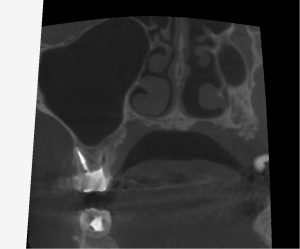

(術後6ヶ月のレントゲン、CT)

今回は全ての根管において、治癒が認められた。

治療前の症状も全て改善され、最終補綴へ移行した。